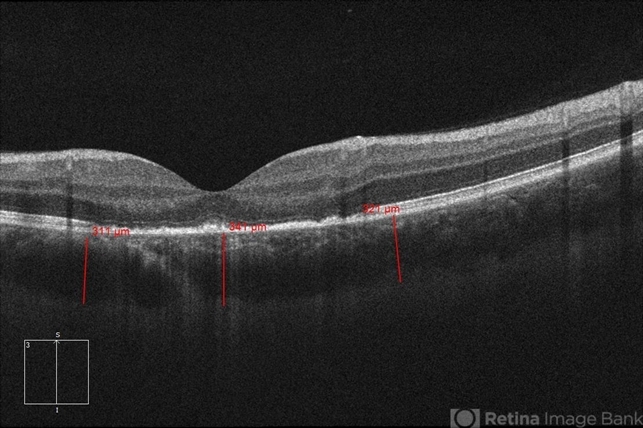

- 20-year-old white, male presented for initial evaluation with one week history of acute, sudden, painless loss of central vision in his right eye a week prior to presentation. - H/O short course of exogenous testosterone, Tamoxifen and Clomiphene intake ~ 2-3 weeks cycle, which was already stopped, prior to development of pt's symptoms. - H/O acute illness with generalized fatigue, malaise, URTI like symptoms and rash over the hands and chest, just prior to symptoms development, and upon further discussion, pt mentioned that few of his friends got sick around the same time. - Patient was seen the week prior by general ophthalmologist and was found to have SRF on OCT , diagnosed with CSCR and referred for retina evaluation. - ROS/ PMHx: Negative, healthy aside from the short illness described above - Denied any prior vision problems, similar episodes, trauma etc - VA Dsc OD: 20/400 OS:20/20 - anterior segment exam - unremarkable - posterior segment - macular RPE changes/ clumping with GA with no CME/ SRF or crystals OD, and unremarkable OS. - Pseudocolor and FAF photos: RPE changes/ clumps w/ GA and stippled autofluorescense OD, unremarkable OS. - HD SD-OCT: thickened choroid, thickened/ hypertrophied subfoveal RPE with hyper-reflective material on the apical side of the retinal pigment epithelium/apical debris, Subfoveal ellipsoid zone atrophy w/ intact ELM W/No CME or SRF OD, Unremarkable OS. - FA: Dye not available - ICG: deferred - mf-ERG & VF - patient rescheduled